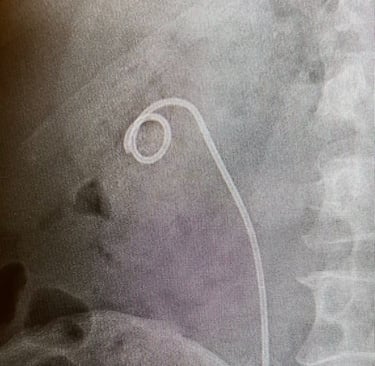

5. Stent Yerleştirme: Üreterin iyileşmesine yardımcı olmak ve idrar akışını sağlamak için işlem sonunda üreteral stent (Double-J stent) yerleştirilebilir.

Fleksible URS + j stent takılması